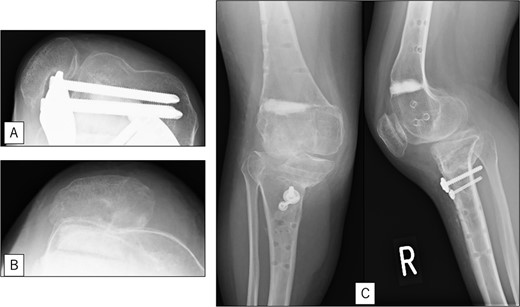

A 23-year-old woman presented with bilateral knee pain and gait abnormalities owing to marked lower extremity deformity. She was diagnosed with EVC as a child but had never been followed up by orthopedics because she was not in pain. On physical examination, marked valgus instability was observed in both knees, and the motion of both knees ranged from 10° to 135°. Radiographic examinations of both knees, including computed tomography, showed valgus deformity, lateral and anterior depression of the proximal lateral tibial plateau, and external rotation deformity of the lower leg. Patellar dislocation was observed in the right knee (Fig. 1). The radiological angles are presented in Table 1. The right knee underwent surgery first, followed by the left 10 months later. Lateral and medial skin incisions were made. Extensive lateral retinacular release, fractional lengthening of the distal lateral hamstring, and Z-lengthening of the iliotibial band were then performed. At this stage, peroneal nerve strain was identified, and decompression of the peroneal nerve was performed. Osteotomy was subsequently performed on the tibia. Closed-wedge varus and derotational osteotomy of the proximal tibia and open-wedge varus osteotomy of the distal femoral varus were performed. In addition, vastus medialis advancement was performed on the right knee, and patellar realignment was achieved in extension (Fig. 2). However, the knee showed a subluxation tendency owing to flexion of >30°; therefore, the postoperative rehabilitation plan progressed more slowly than that of the left knee. Range of motion training began on the left knee immediately after surgery without any restrictions, but on the right knee only after 3 weeks of postoperative immobilization in the extended position. However, ambulation exercise was performed on both knees with no loading for 3 weeks, then partial loading was initiated, and full loading was permitted at 8 weeks postoperatively. Early postoperative standing radiography showed residual mild valgus deformity of the lower limbs (Fig. 2, Table 2). In addition, the right knee showed patellar re-dislocation 2 months postoperatively, and the patellar deformity gradually progressed owing to the femoral implant; therefore, the patient underwent implant removal, tibial tubercle transfer, and medial patellofemoral ligament reconstruction 1.5 years after the initial surgery (Fig. 3). Six months later, she fell while walking and developed a fracture at the osteotomy of the right femur; open reduction and internal fixation were performed (Fig. 4). The remaining years passed uneventfully, and 10 years after the initial surgery, the patient still had mild valgus deformity of the lower limbs, but had no recurrence other than that experienced immediately after surgery, no complaints of knee pain, and a stable gait (Fig. 5, Table 2).

Postoperative radiography: (A) immediate postoperative radiograph of the right knee, (B) immediate postoperative radiograph of the left knee, (C) the entire lower limbs at 2 months after left knee surgery. Mild valgus deformity of the lower limbs persisted.